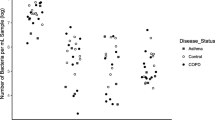

Several studies have reported background contamination in microbiota data generated from respiratory specimens with low bacterial load (< 106 bacterial cells/mL of specimen) [3, 4, 7, 8, 18, 21]. Factors that determine the bacterial load in respiratory specimens include the specimen type (e.g. sputum, bronchoalveolar lavage [BAL], swabs), the specimen volume, the anatomic site sampled (e.g. upper or lower airways) and clinical parameters (e.g. age, acute infection, exacerbation, antibiotic use).

Establishing a standardized methodology for low bacterial load specimens requires consideration of differences in patient populations and specimen types. Many microbiota studies are designed to compare the microbiota present at high bacterial load in all study groups, e.g. gut microbiota studies. In respiratory studies, bacterial load can be more variable with low bacterial load specimens more common in some groups than others. For example, lower airway microbiota in healthy controls compared to that of patients with chronic lung disease [34], or bacterial load variations between groups defined by antibiotic exposure [27, 35], or respiratory sites [7, 31]. Bacterial load is also important because specimens containing few bacteria may be excluded from downstream analyses if insufficient amplicons or sequence reads are generated. This exclusion risks loss of statistical power by reducing the sample size or by introducing imbalances to the study design that may affect downstream analyses.